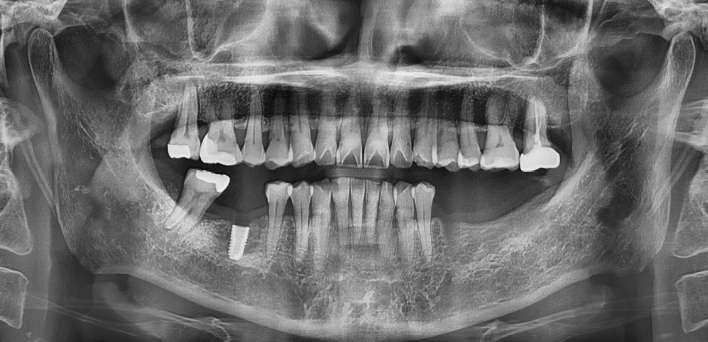

임플란트 케이스

임플란트 Before & After

The seoul dental clinic

치료 기록 더보기버튼

※ 더서울치과의원은 의료법을 준수하며 위 케이스는 실제 환자의 동의를 얻은 사례로 치료 전, 후가 동일한 환경에서 촬영되었습니다.

환자 케이스에 따라 부작용이 발생할 수 있습니다. 이 부분은 의료진의 충분한 상담과 체크를 통해 예방하고 줄일 수 있습니다.

[임플란트 부작용] 수술 후 관리가 소홀할 경우 출혈, 주위염 등의 부작용이 발생할 수 있어 구강 위생을 철저히 유지하고, 정기적인 검진을 통해 상태를 점검하는 것이 중요합니다.